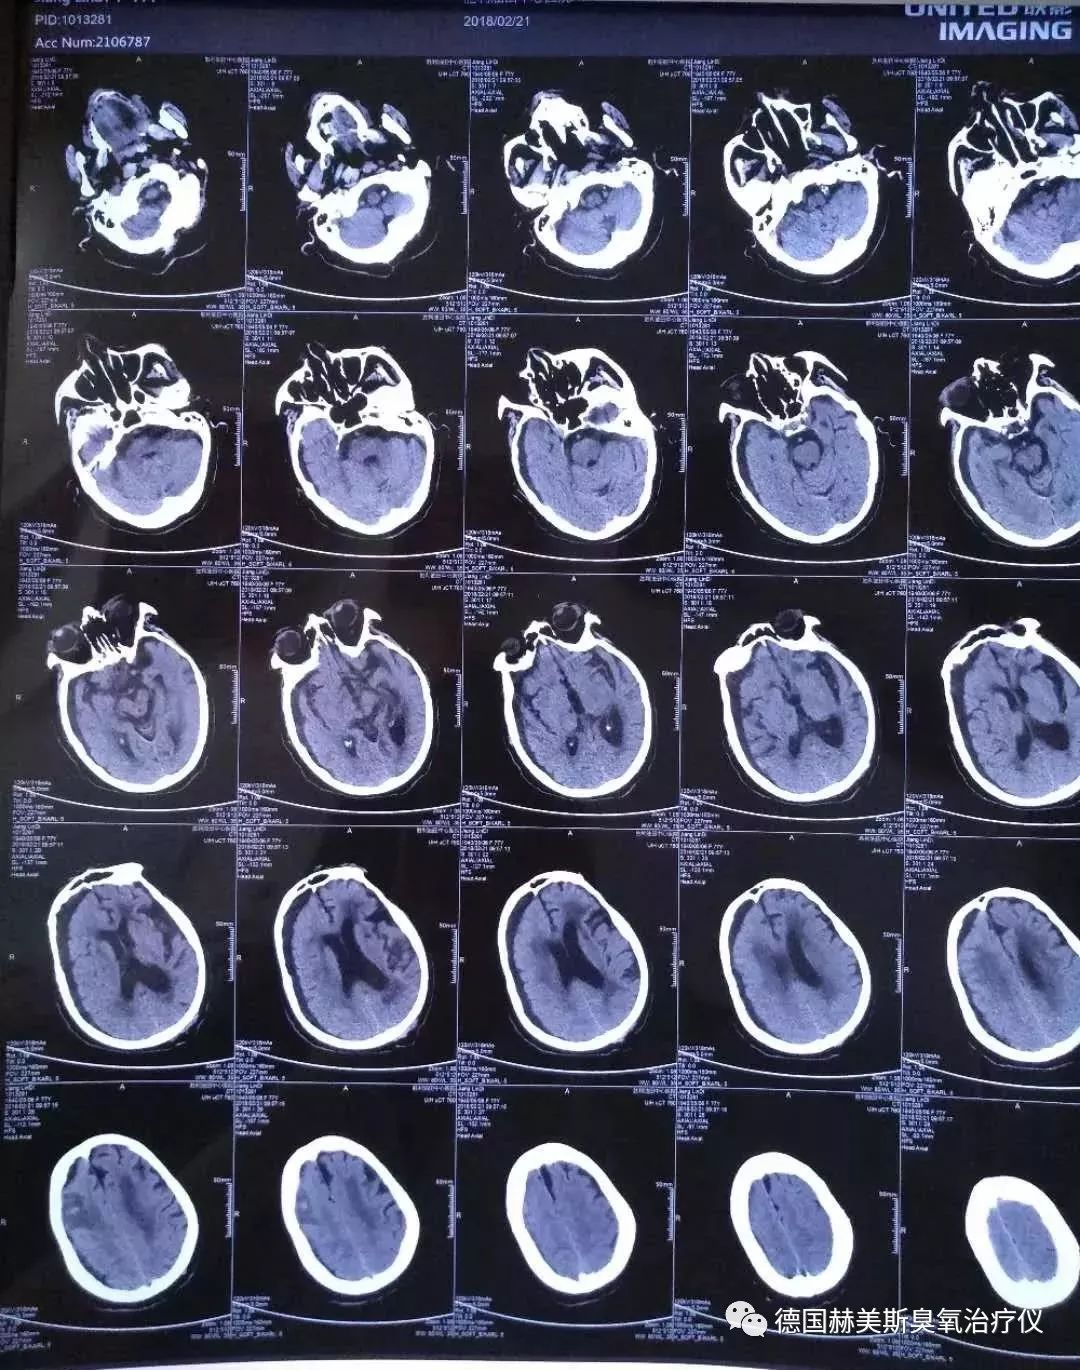

患者入院时颅脑影像

三个月前患者因不慎摔倒后出现意识障碍,头痛头晕,偶有恶心呕吐,行走不能,二便*禁失**,在当地医院住院治疗,颅脑MRI和颅脑CT显示:脑梗塞、硬膜下积液、脑萎缩; 住院给予营养脑神经、改善脑细胞代谢、脱水等治疗,经治疗患者病情无明显变化,继续加重。为求进一步治疗,遂来我院。

入院后刘教授详细查体和仔细询问病史,给予诊断:1、脑梗塞;2、硬膜下积液;3、外伤性脑出血待排;4、脑萎缩;5、2型糖尿病;6、原发性高血压